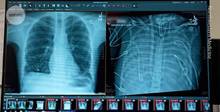

Мужчина потерял легкие из-за гриппа и двое суток прожил без них. Как это возможно?

Инженеры, ученые и медики многие годы пытаются создать систему, которая могла бы заменить «вышедшие из строя» легкие: к настоящему времени существуют подобные решения, однако их применение ограничено. Новая разработка, спроектированная и реализованная группой специалистов и уже проверенная в деле, не станет панацеей, однако позволит изменить ситуацию, повысив шансы пациентов на выживание. Читать далее…